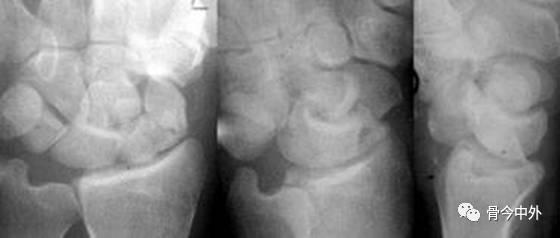

图1 成人期腕关节正侧位及舟骨蝶位片。1.舟骨;2.月骨;3.三角骨;4.豆状骨;5.大多角骨;6.小多角骨;7.头状骨;8.钩骨;9.桡骨茎突;10.尺骨茎突;11.第一掌骨基部。

图2 成人期腕关节正侧位及舟骨蝶位片。1.舟骨;2.月骨;3.三角骨;4.豆状骨;5.大多角骨;6.小多角骨;7.头状骨;8.钩骨;9.桡骨茎突;10.尺骨茎突;11.第一掌骨基部。

图3 成人期腕关节正侧位及舟骨蝶位片。12.舟骨结节。黑色箭头:舟骨腰部;白色箭头:舟骨滋养血管影。